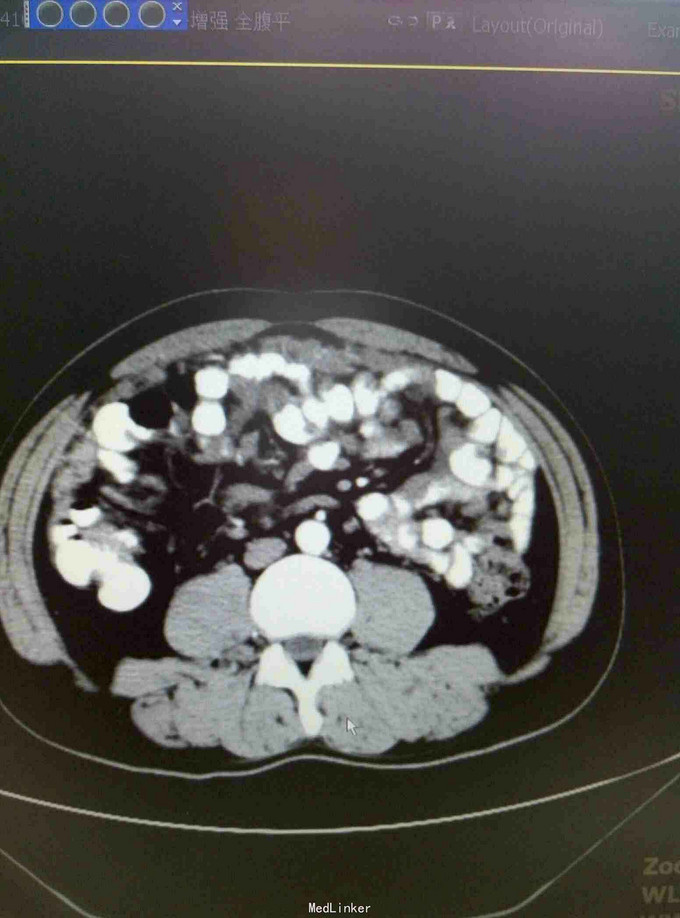

患者15年6月因腹胀就诊某医院行CT:疑似自发性腹膜炎,给予抗炎治疗。9月15日送检腹水发现增生间皮细胞。后去省影像中心行CT示:腹膜广泛增厚,强化,符合转移。后就诊我院腹膜肿物穿刺病理:促结缔组织增生性小园细胞瘤。后期贝伐单抗,IFO,THP,VCR,治疗。目前治疗中……